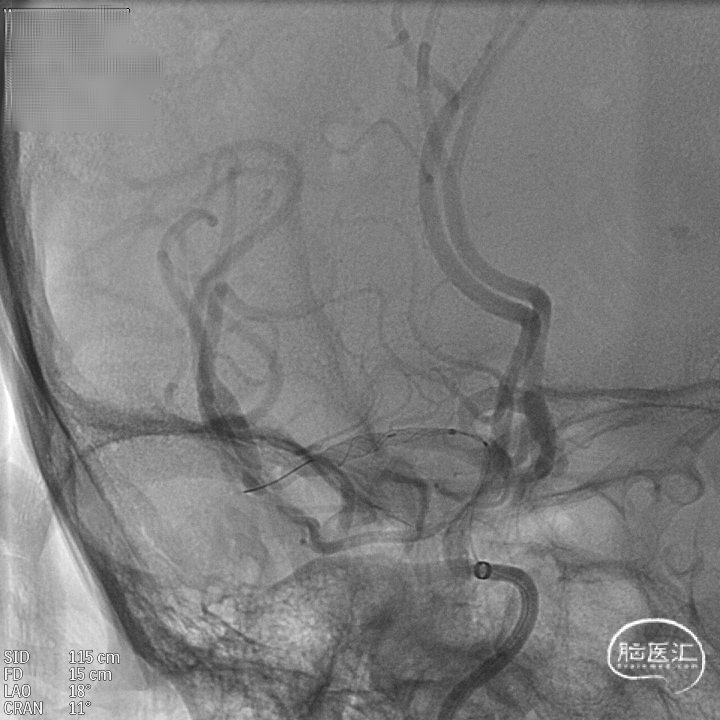

微导管到位:Synchro微导丝引领支架微导管通过病变血管进入大脑中动脉M2段。

支架到位,原位释放,前段打开。

造影确认支架远端打开充分,贴壁良好,继续推送支架。

支架全部释放,调整张力,微导管通过支架,回收输送导丝。

支架内使用成襻微导丝进行按摩,使支架充分贴壁。

术后造影:支架充分覆盖动脉瘤瘤颈,贴壁良好,瘤体内可见造影剂滞留。

术后支架显影:定位精准,未覆盖颞前动脉及大脑前动脉。